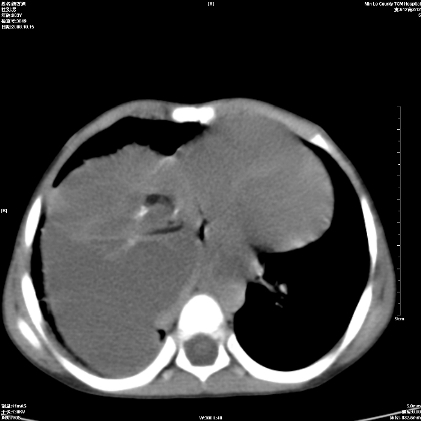

标题: PED1609:男性,3岁。彩超示肝Ca. [打印本页]

标题: PED1609:男性,3岁。彩超示肝Ca.

考虑后纵隔恶性畸胎瘤伴肝内多发转移可能性大,右侧肾上腺转移不除外.

3岁;肝低密度灶;有钙化;有转移灶;考虑肝母细胞瘤;查afp

考虑神经母细胞瘤并肝转移

考虑:1、右侧后下纵隔畸胎瘤。

2、肝脏多发血管内皮细胞瘤。

建议:增强确诊。